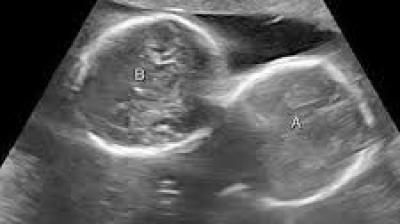

सतना जिले में एक पुरुष के पेट में मिला ‘गर्भाशय…. सोनोग्राफी रिपोर्ट हो रही वायरल

21 Jan, 2026 08:26 AM IST | SALILSANDESH.COM

सतना। मध्यप्रदेश (Madhya Pradesh) अजब है, सबसे गजब है। यह टैगलाइन सतना जिले (Satna district) में एक बार फिर सच साबित हुई है। यहां के एक डायग्नोस्टिक सेंटर (Diagnostic center)...